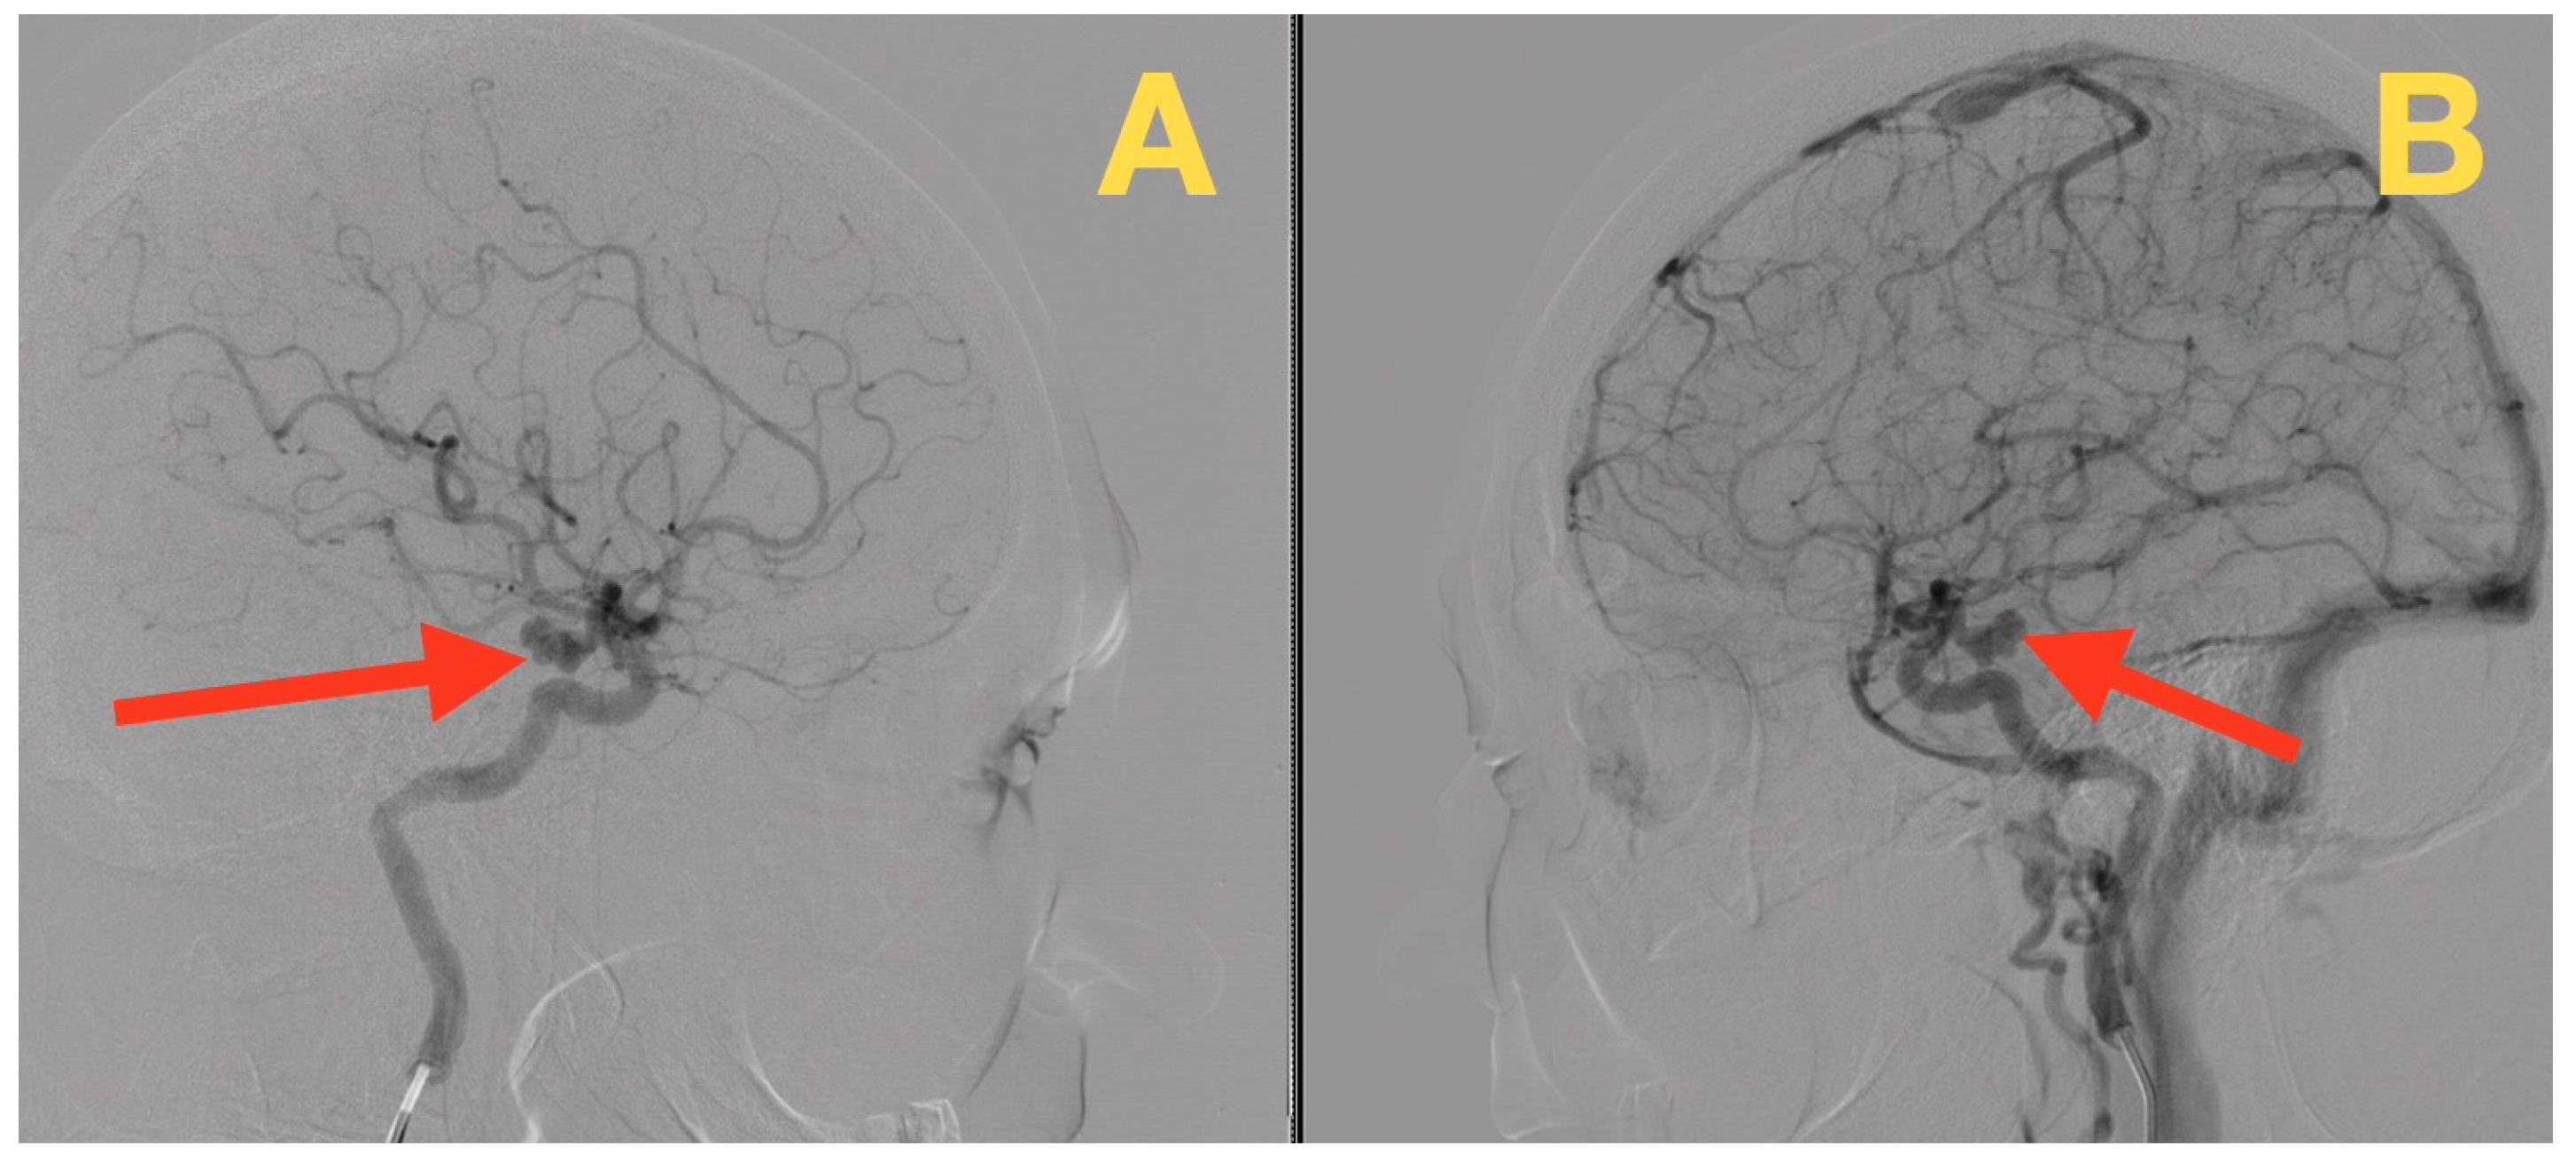

2. Case Presentation